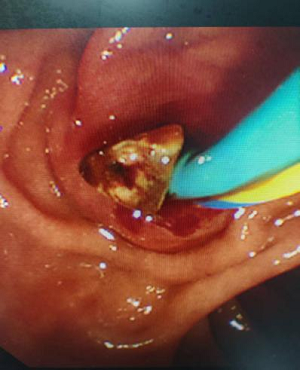

取出结石